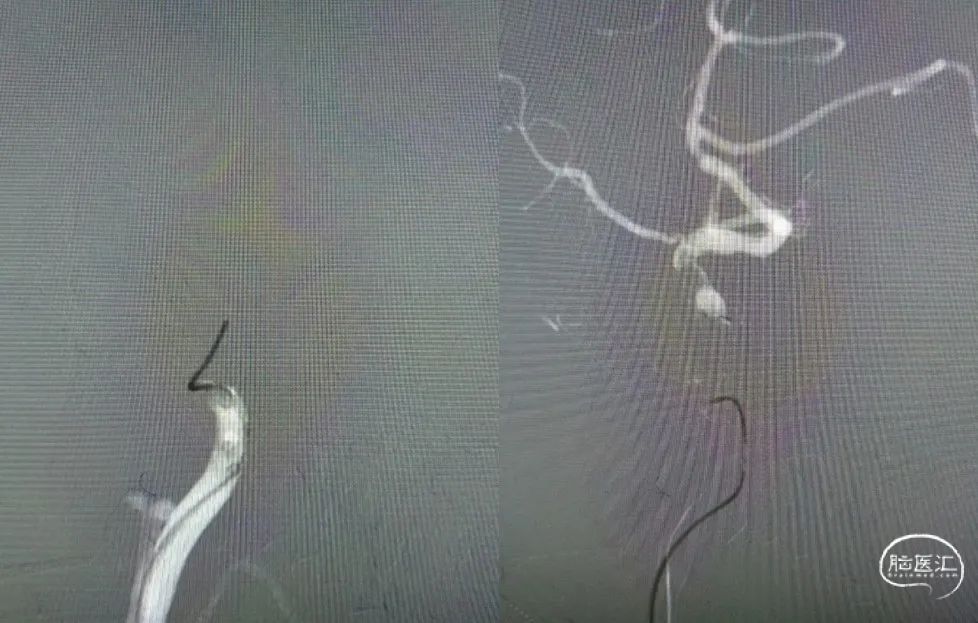

利用赛诺神畅 NOVA DES®颅内药物洗脱支架锚定后释放,血管再通,mTICI 3级,局部动脉给药替罗非班(0.2ug/kg.min)约3ml,持续15分钟。静脉(0.1ug/kg.min)持续泵入24小时后改为口服双抗。

支架通过病变。

支架释放。

术后影像及检查

术后正位造影。

术后侧位造影